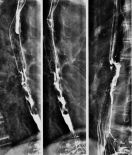

Während Sie den Kontrastmittelbrei (Bariumsulfat – Prontobario HD) schluckweise trinken, beobachtet der Radiologe unter Durchleuchtung am Monitor, wie das Kontrastmittel durch die Speiseröhre fließt. Anschließend wird in liegender Position überprüft, ob ein Rückfluss vom kontrastmittelgefüllten Magen zurück in die Speiseröhre erfolgt (sogenannte Refluxerkrankung).

Im Videoschluckakt kann speziell auch die Schleimhaut der Speiseröhre beurteilt und anhand der Videoaufzeichnung Schluckstörungen analysiert werden.